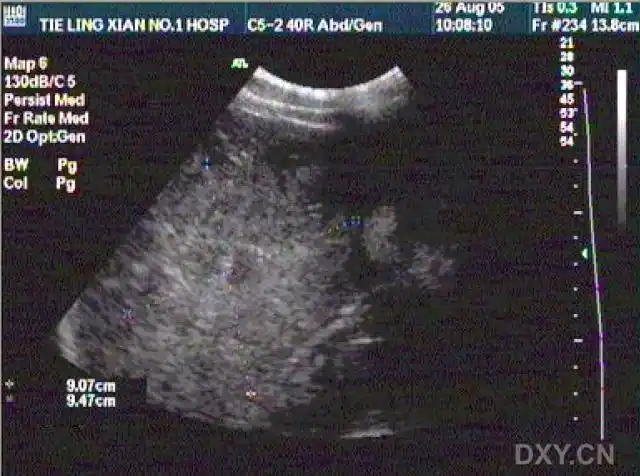

【超声】肝破裂超声,请战友欣赏